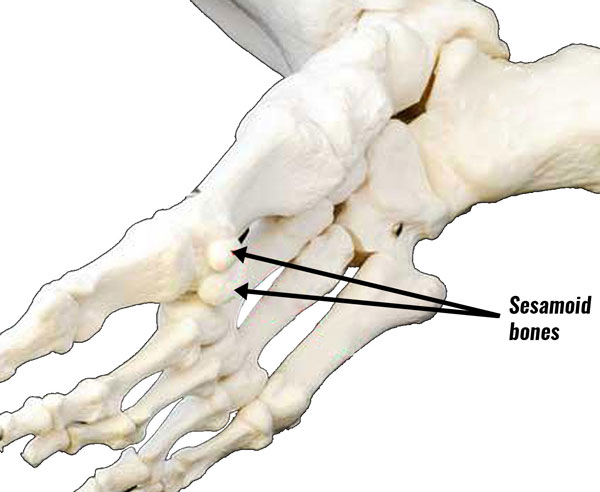

Перелом сесамовидной кости: Визуализация травмы и её лечение